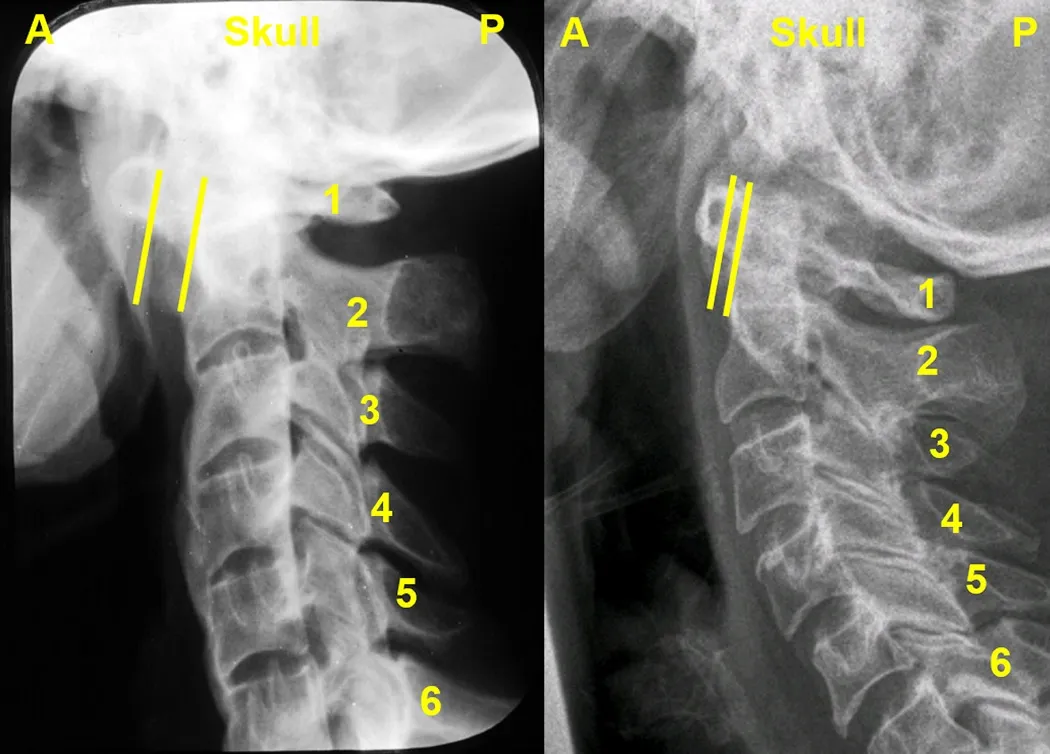

Common Image Processing Techniques 1 is a first year course in the Edinburgh Imaging Academy’s post-graduate Neuroimaging for Research MSc / Dip / Cert. It can also be taken not-for-credit as CPD / CME. Image The changing measure of atlanto-axial subluxation between flexion and extension views. Our online Common Image Processing Techniques 1 (CIP1) short course teaches common image evaluation techniques, ranging from: qualitative & quantitative whole brain / sub-regional brain volume assessment simple & complex lesion size evaluation plus region of interest measurements to assess tissue parameters acquired by MR imaging. You can download our syllabus, which includes all the learning objectives for each module and lecture, here: Document Edinburgh Imaging Academy - Common Image Processing Techniques 1 [20 credits] (280.26 KB PDF) (280.26 KB / 26 KB PDF)) We offer multiple options for studying Common Image Processing Techniques 1: As a stand-alone course gaining University credits: Starts in January / Winter / Semester 2 20 University credits As a stand-alone course, without University credits for CPD / CME preparation: Starts anytime Embedded in one of our online degree programmes: Neuroimaging for Research MSc / Dip / Cert We asked Dr Susana Muñoz Maniega, Research Fellow in brain imaging and main tutor for the Common Image Processing Techniques 1 course, to describe the course in more detail: Who is the CIP1 course aimed at? This course is aimed at students with an interest in learning about the different methods used to perform quantitative and qualitative assessments of the brain images. The course starts from basic concepts and is suitable for students from both technical and clinical backgrounds. What can you learn in the CIP1 course? The course starts off explaining the basic concepts on how and why measurements are made from radiological images in general, and what the potential sources of error are that could affect these measurements. It then focuses on specific techniques to perform measurements of brain volumes and assessment of brain changes commonly seen in brain images, such as white matter hyperintensities or atrophy. Quantitative and qualitative methods, such as visual ratings and volume assessments, are explained in detail, and the advantages, disadvantages and suitability of each technique are discussed. The students are given practical examples to apply these methods and compare them, as well as learning about what factors contribute to measurement accuracy, consistency and reproducibility. There are opportunities for discussion with their peers in group activities. There is also a module discussing the reasons and practical implications of combining datasets and multicentre studies. What benefits can you get from our online study options? The students can ask any questions in the course discussion forums at any time. These are supported by expert tutors, who can answer questions and provide a means for discussion with other students. The modules, extra material and forums are always available, providing maximum flexibility for the students, who can work on the course whenever is more convenient. There are two in-course activities which allow the students putting their knowledge into practice. These include individual and group work, where the students are encouraged to collaborate and discuss with their groupmates. What outcomes / what can you expect at the end of the CIP1 course? At the end of the course, the students will be able to describe and put into practice some of the techniques used in clinical and research settings to assess brain volumes and common brain changes. They will also develop awareness of the suitability of each technique, as well as potential sources of error and the implications of these. This would allow the students to make informed decisions about the methodology more suitable in different research and clinical scenarios. Relevant links Dr Susana Muñoz Maniega Common Image Processing Techniques 1 (CIP1) Edinburgh Imaging Academy Short courses Degree programmes Training tools About our students What is a MR scan? In the news: 17 May 22. EUSA Teaching Awards 28 Apr 22. Online learning: Translational imaging & clinical trials 28 Mar 22. Online learning: Cardiovascular imaging 25 Feb 22. Online learning: Hybrid radionuclide imaging (PET-MR) 27 Jan 22. Online learning: Study design 15 Dec 21. Online learning: Practicalities & safety 06 Dec 21. EIA January admissions 29 Nov 21. Online learning: Anatomy (body) 27 Oct 21. Online learning: Anatomy (neuroanatomy) 27 Sep 21. Online learning: Statistics 15 Sep 21. National Online Learning Day 27 Aug 21. Online learning: Clinical applications 27 Aug 21. Online learning: Applications in disease 27 Jul 21. Online learning: Techniques & physics 18 Jun 21. PET-MR neuroimaging course 15 May 21. New cardiac imaging educational resource 11 May 21. ACTATS one year on 21 Dec 20. Tutor of the Month 13 Aug 20. ACTATS milestone 07 May 20. ACTATS goes live 25 Nov 19. Edinburgh Imaging Academy graduations Social media tags and titles Common Image Processing Techniques 1 is a first year course in the Edinburgh Imaging Academy’s post-graduate Neuroimaging for Research MSc / Dip / Cert. It can also be taken not-for-credit as CPD / CME. @EdinUniMedicine @uoe_online Publication date 19 May, 2022